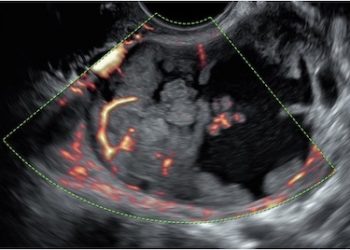

Cari soci, finalmente online le soluzioni dei casi del mese di Giugno!!! Grazie a Valentina D'Ambrosio e Alba Piras!! Caso...